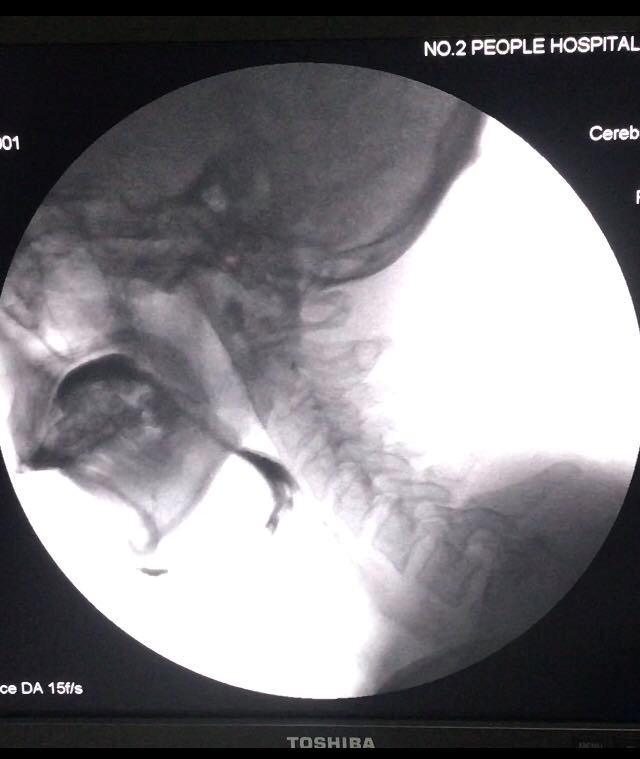

辅助检查 (1)电视荧光吞咽造影检查(videofluroscopic swallowing